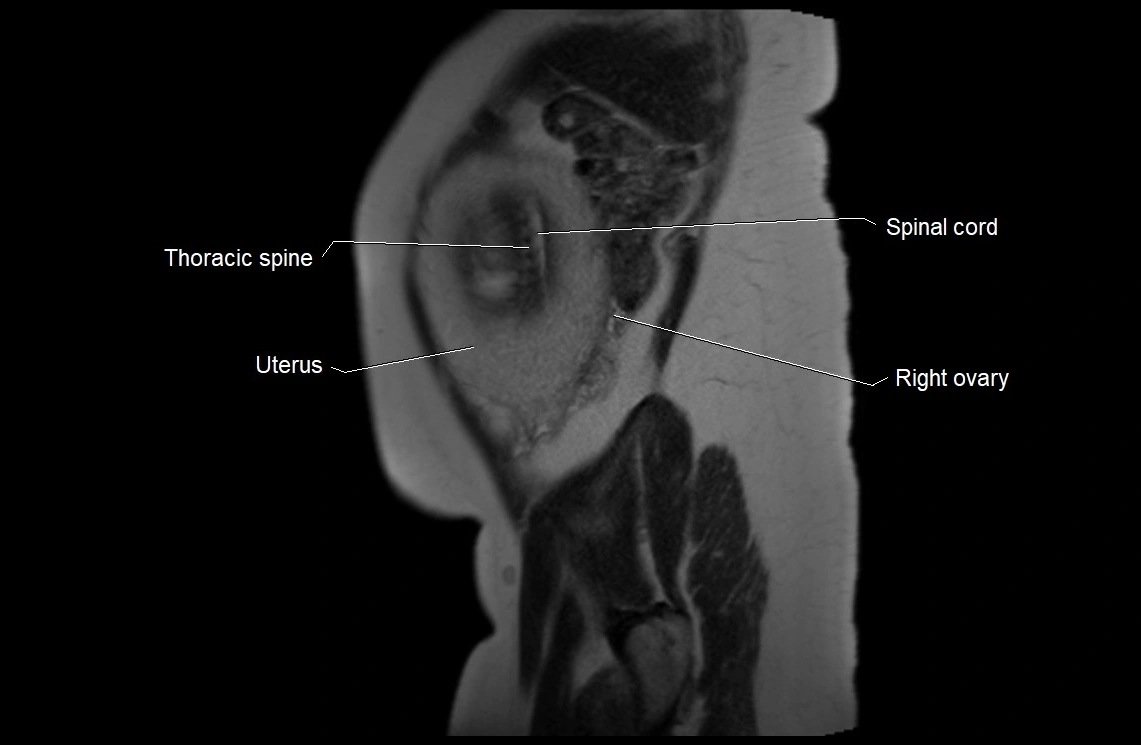

MRI Appearance

T2 HASTE (T2 GRE):

• Amniotic fluid shows very bright hyperintense signal

• Provides natural contrast against fetus and placenta

• Small particles (vernix) may appear as scattered hypointense foci within bright fluid

T1 GRE:

• Amniotic fluid shows low signal intensity (dark)

• Hemorrhage, infection, or proteinaceous content may cause focal or diffuse high signal intensity

MRI image

image